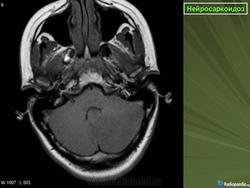

ID: 17921 Neurosarcoidosis Dr Frank Gaillard - 25 May 2012 The case demonstrates typical features of neurosarcoidosis, which are of...

Случай 1: с участием лептоменинга